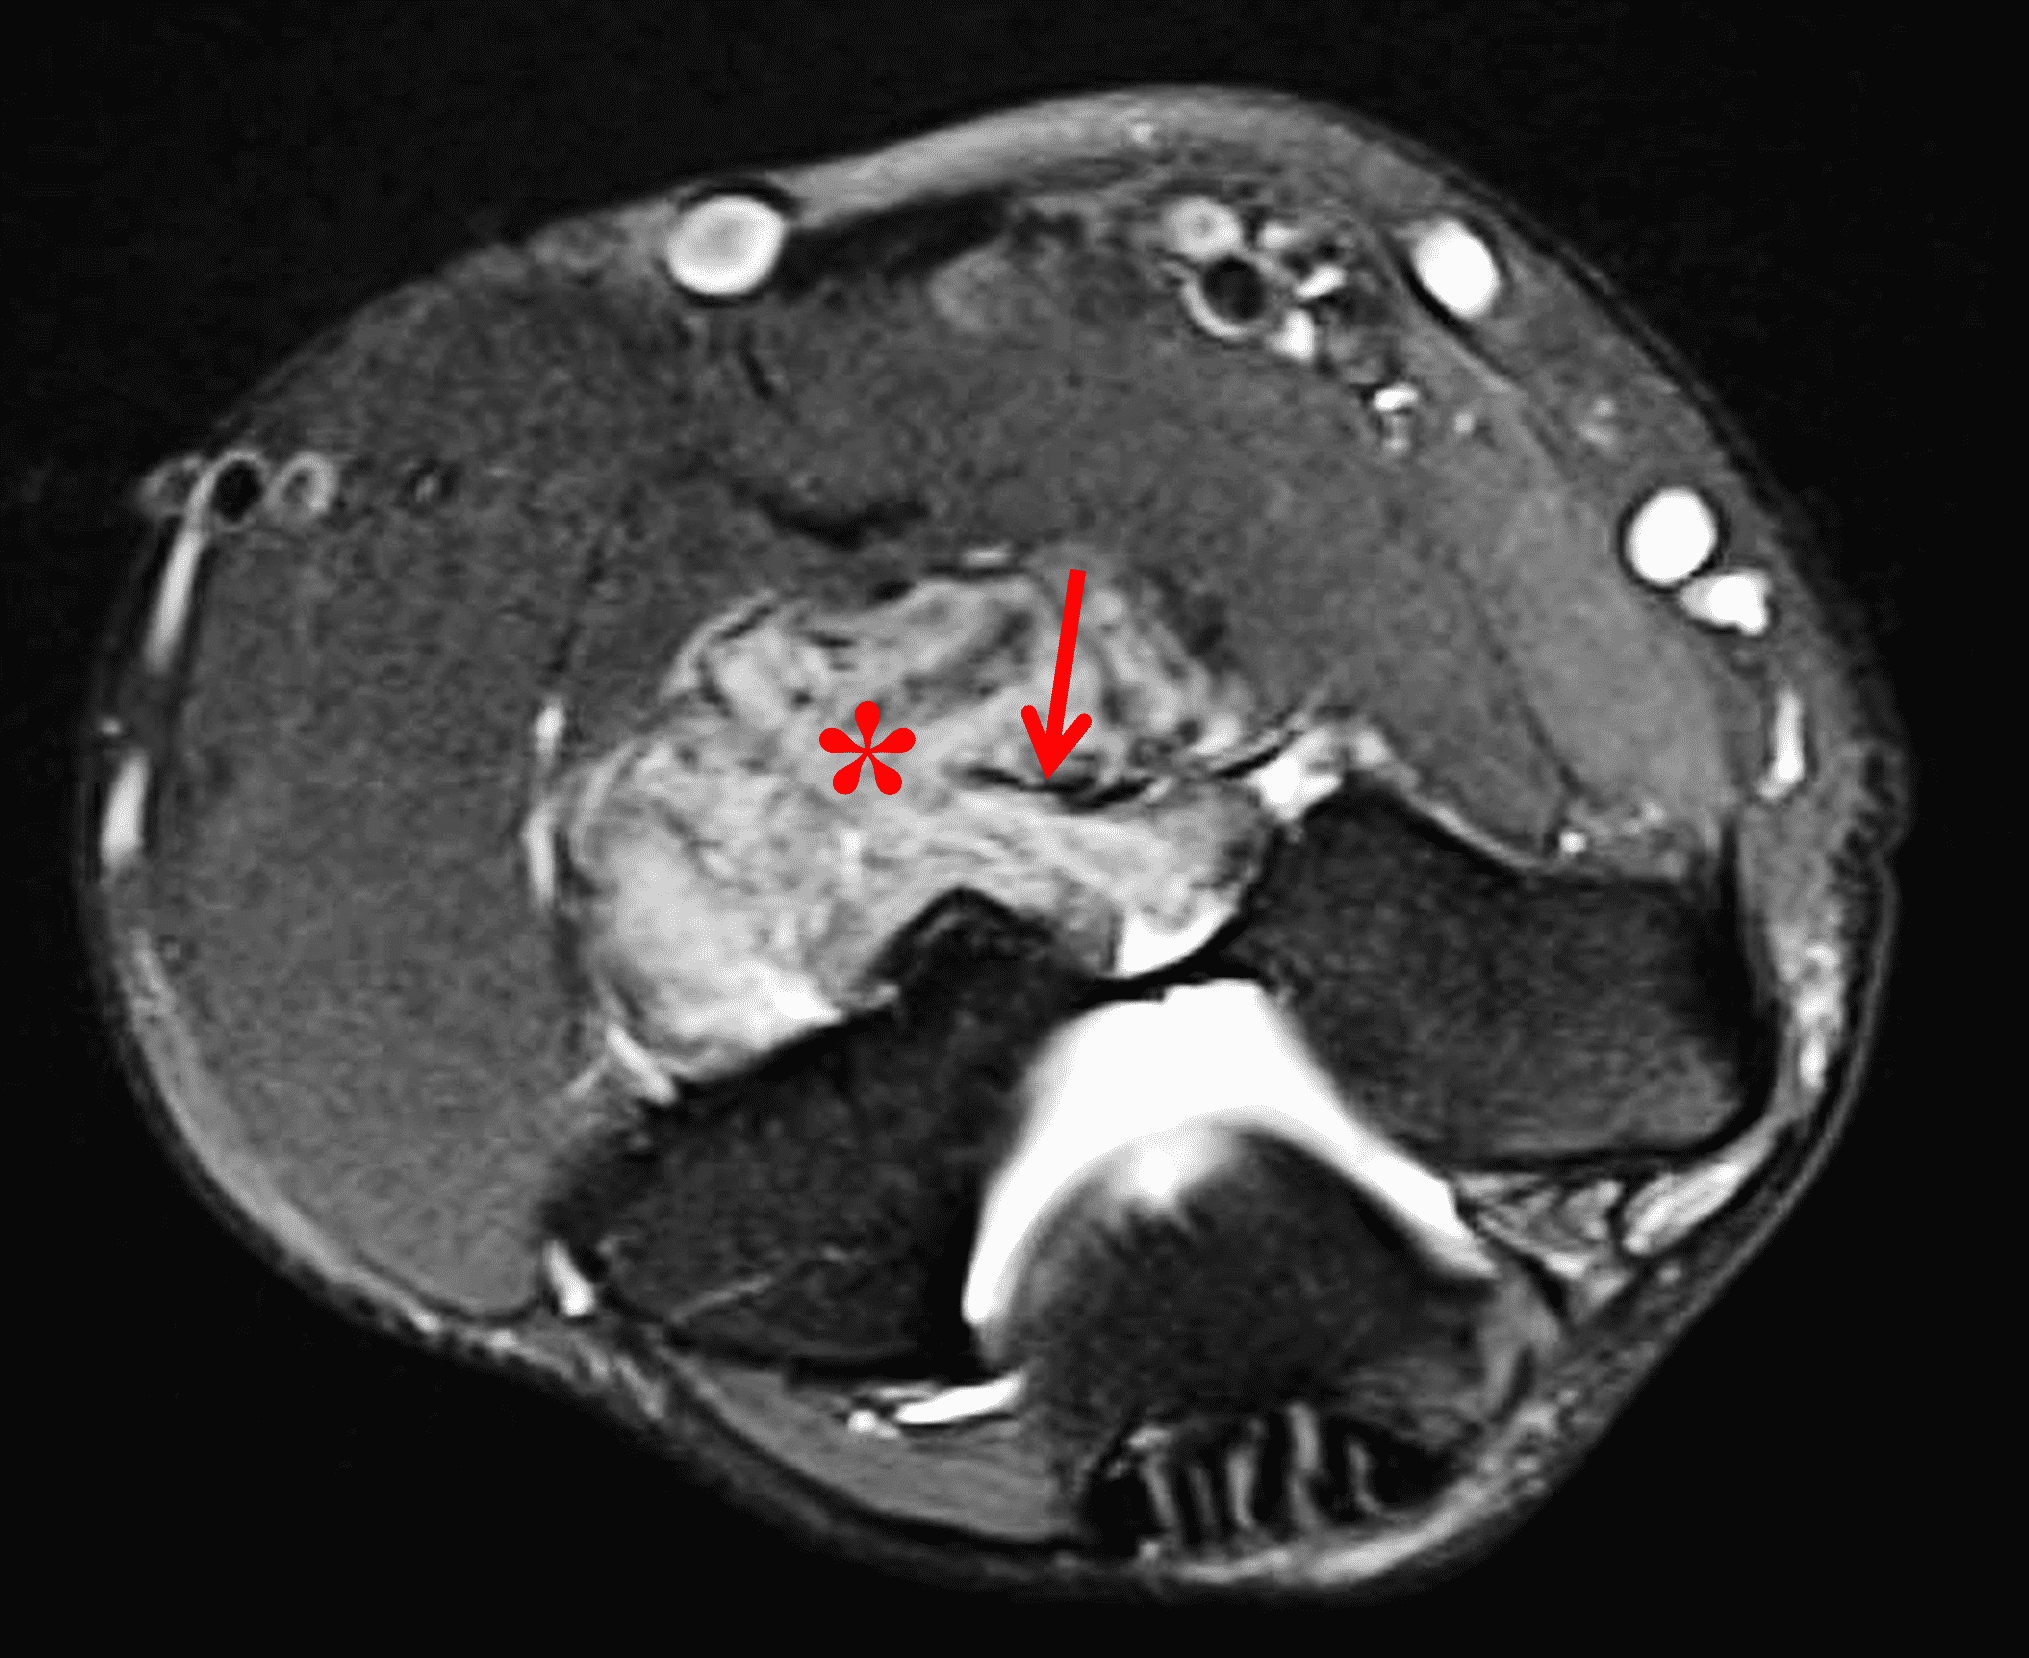

Gout (https://radsource.us/gout/) is the most common metabolic crystalline deposition disease, characterized by monosodium urate crystal deposition in joints and soft tissues in patients with long standing hyperuricemia.2–4,16,17 It most commonly occurs in the first metatarsophalangeal joint and is more common in men, presenting most frequently in the fifth decade. Early disease is usually monoarticular, but location, duration and frequency of attacks increase with disease progression. Gout occurs in idiopathic, secondary, and drug-induced forms, and can also be divided into acute, intermediate and chronic forms by imaging.2-4,16,17 With acute flares, patients present with pain, swelling and erythema about a joint, bursa or tendon sheath, typically lasting 24-48 hours and resolving by 5-7 days. Crystals remain in the joint, predisposing to subsequent attacks due to chronic low-grade inflammation. Tophus formation is almost always a manifestation of chronic gout, although some cases of tophi have been described in the acute setting. Tophi are composed of urate crystals, protein matrix, inflammatory cells and foreign body giant cells. Tophus deposition can be intra-articular or extra-articular, and can involve cartilage, bone, ligaments, tendons and subcutaneous tissues.2-4,16,17

Imaging characteristics are variable in different stages. On radiographs, in early stages, soft tissue swelling may be the only finding. With chronic gout, intra-articular or juxta-articular erosions with overhanging edges, and soft tissue mass with or without calcification can be seen, with relative preservation of joint spaces until late stage of disease.2-4,16,17 On MRI (Figures 2 and 9), tophi usually appear as intermediate T1 signal masses with variable T2 signal depending on the amount of calcification present, and somewhat variable contrast enhancement. On CT, tophi are usually hyperattenuating with or without calcifications. Gout may also present on imaging as focal or multifocal disease within a joint.2-4,16,17

Figure 9: Tophaceous gout in the knee. (9A) Coronal fat-suppressed, fluid-sensitive image demonstrates heterogeneous intermediate signal intra-articular masses (red arrows). Hypointense foci (yellow arrows) correspond to calcifications. (9B) AP radiograph confirms calcification within the tophi (arrow) as well as meniscal chondrocalcinosis.